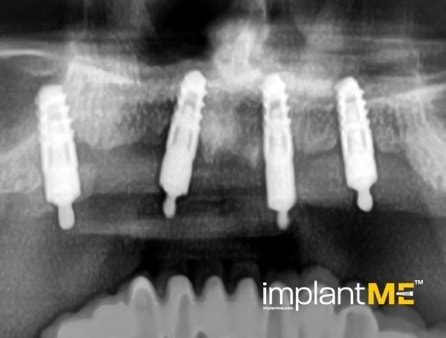

Атрактивните и особено здравите заби не се само одлучувачки дел од нашиот изглед, туку и на нашата личност. Во минатото, губењето на еден или повеќе заби имаше одлучувачка улога врз изгледот на луѓето. Поради модерната орална имплантологија, ова повеќе не е случај. Со релативно мали процедури за орална хирургија, индивидуалните или сите непостоечки заби можат да бидат заменети со импланти, естетски и функционално еднакви на природните заби. Преку вметнување импланти во форма на корен, можно е да се избегнат промени на соседните заби и да се зацврстат коронки што тешко може да се разликуваат од вистински заби во празнините на забите. Коронките или мостовите поддржани од импланти се прицврстени на колец зацврстен во коска, што им дава на пациентите џвакање со чувство скоро нималку различно од нивните заби. Во случај на потполна беззабост, имплантите може да претставуваат сигурна потпора за мобилна протеза, како и за големи фиксни мостови.

Забната протетика поддржана од имплант тесно се доближува до природните заби. Коронките водат со нивниот природен изглед, имплантите со нивната стабилност, а двете заедно со нивното позитивно влијание врз функционалното зачувување на целиот мастикаторен апарат.